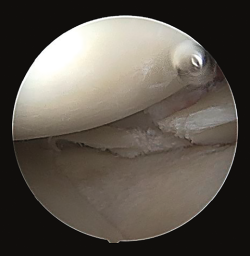

Figure 4. Arthroscopy views from the anterolateral portal, showing bone avulsion with a fragment of the medial root (A), suture advancement through the meniscal root (B), and bone avulsion reduced in its bone bed (C).

Arthroscopy confirmed the diagnosis by visualizing the avulsed root and bone fragment at medial level (Figure 4A) and the radial lesion of the external root (Figure 5). Palpation of both roots evidenced clear instability. The ACL was greatly affected, with subtotal rupture, while the PCL presented correct stability in response to palpation and testing.

The medial root avulsion fracture was repaired using a standard transtibial pullout technique(1,3,6). Suturing required the use of no. 2 FiberWire® (Arthrex, Naples, FL, USA ) through the root with the Knee Scorpion™ system (Arthrex, Naples, FL, USA) (Figure 4B). A FlipCutter® III retrograde reamer (Arthrex, Naples, FL, USA) with a Unicorn Meniscal Root (UMR) guide (Arthrex, Naples, FL, USA) was used to drill a blind tibial tunnel, 6 mm in diameter and 15 mm in length, from the bone bed of the medial meniscus towards the anteromedial tibial cortical layer. The meniscus sutures were retrieved through the trans-bone tunnel with a FiberStick® (Arthex, Naples, FL, USA). The suture was knotted through a metal button, securing correct reduction of the meniscal avulsion (Figure 4C).